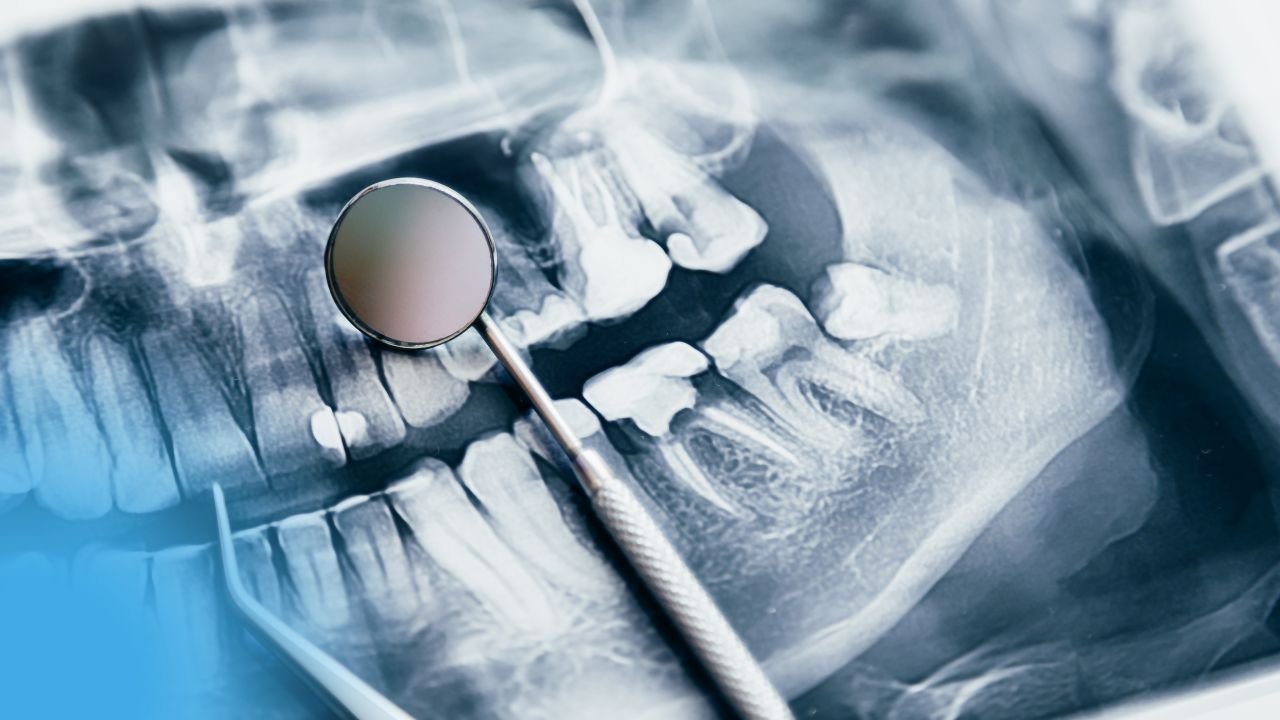

IV. Examen radiologique

Évaluation du parodonte profond :

- Trabeculation osseuse et degré de résorption

- Élargissement desmodontal

- Forme, profondeur et direction des racines

- Rapport couronne/racine

- Qualité des traitements endodontiques